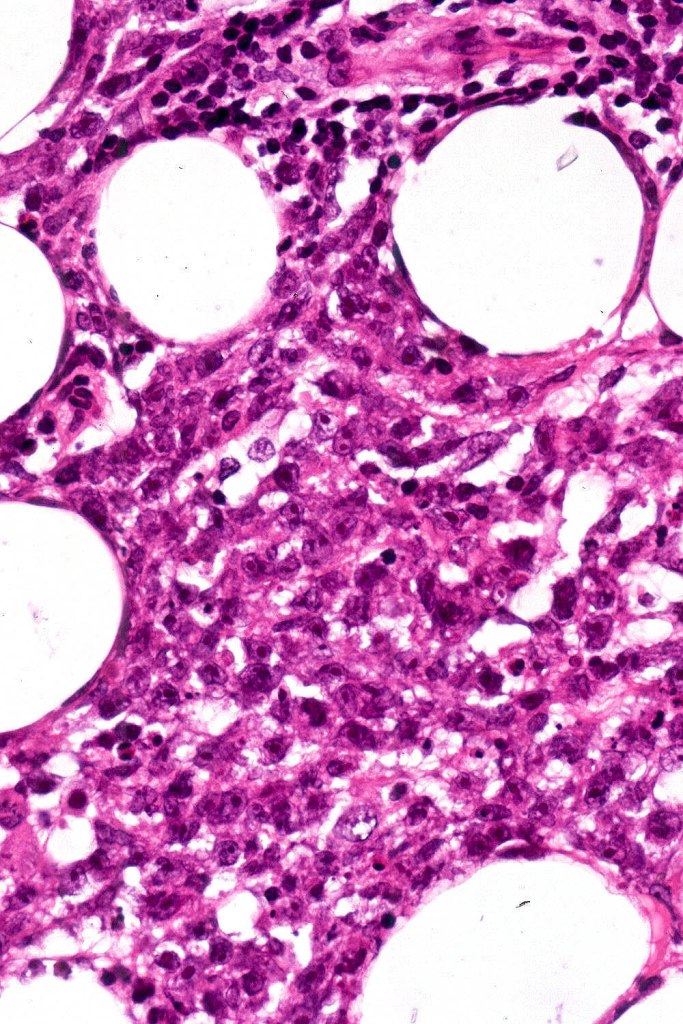

•Dense nodular or diffuse infiltrate of small to large atypical lymphocytes

•Angiotropism, angiodestruction, thrombi & coagulative necrosis